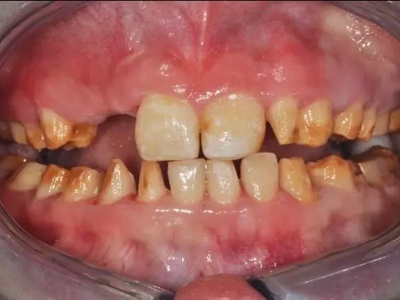

牙釉质发育不全牙齿棕色有缺损图

牙釉质发育不全患者牙齿出现明显的缺损表现,并于表面形成深褐色的蜂窝状、竖条状的凹坑,甚至形成洞,患者上下牙失去咬合能力。